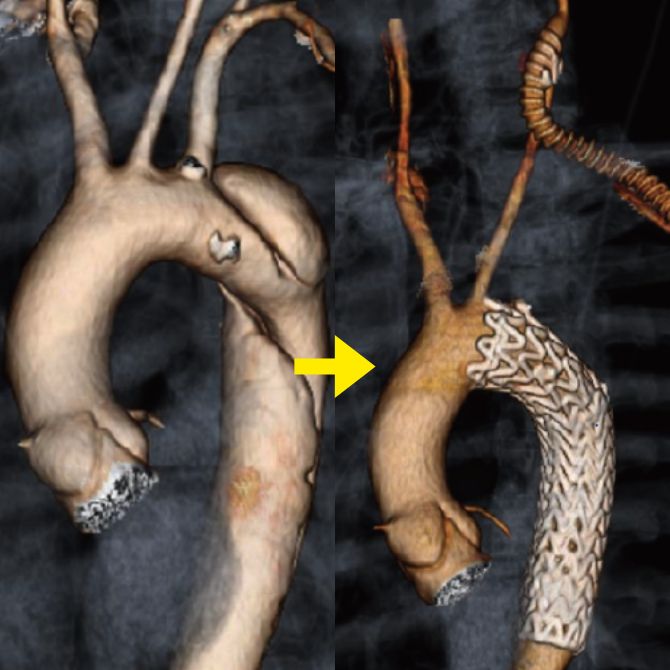

胸部大動脈瘤に対して施行したステントグラフト内挿術

当院では大動脈解離の治療法にオープンステントグラフトを導入しています。オープンステントグラフトは広範囲の解離部分に対して治療効果が得られる利点があります。

解離した場合によっては、ステントグラフト治療が適応になることがあります。大動脈解離に対するステントグラフト治療は専門性が高く、心臓血管に特化した当院の大動脈専門スタッフが慎重に判断して施行しています。

当院では豊富な経験により多くの方に治療を施行しております。特にハイブリッド治療と呼ばれる「血管バイパス手術とステントグラフト治療」を組み合わせた治療があり、体への負担を最小限に抑えた方法です。他院で治療が困難といわれた大動脈瘤・大動脈解離の方も、お気軽にご相談下さい。